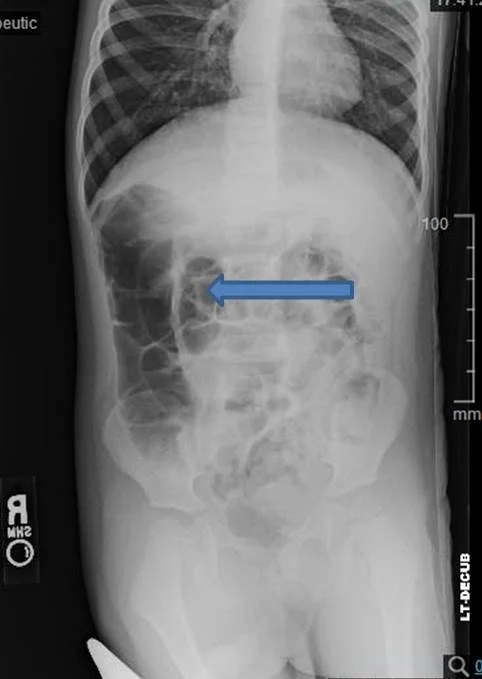

Intussusception Axr Target Sign - Can show small bowel obstruction, currarino’s sign of not seeing air in hepatic flexure of colon, usually unremarkable so normal axr does not rule out intussusception us:

Can show small bowel obstruction, currarino's sign of not seeing air in hepatic flexure of colon, usually unremarkable so normal axr does not rule out intussusception us:

The target sign of intestinal intussusception, also known as the doughnut sign or bull's eye sign.